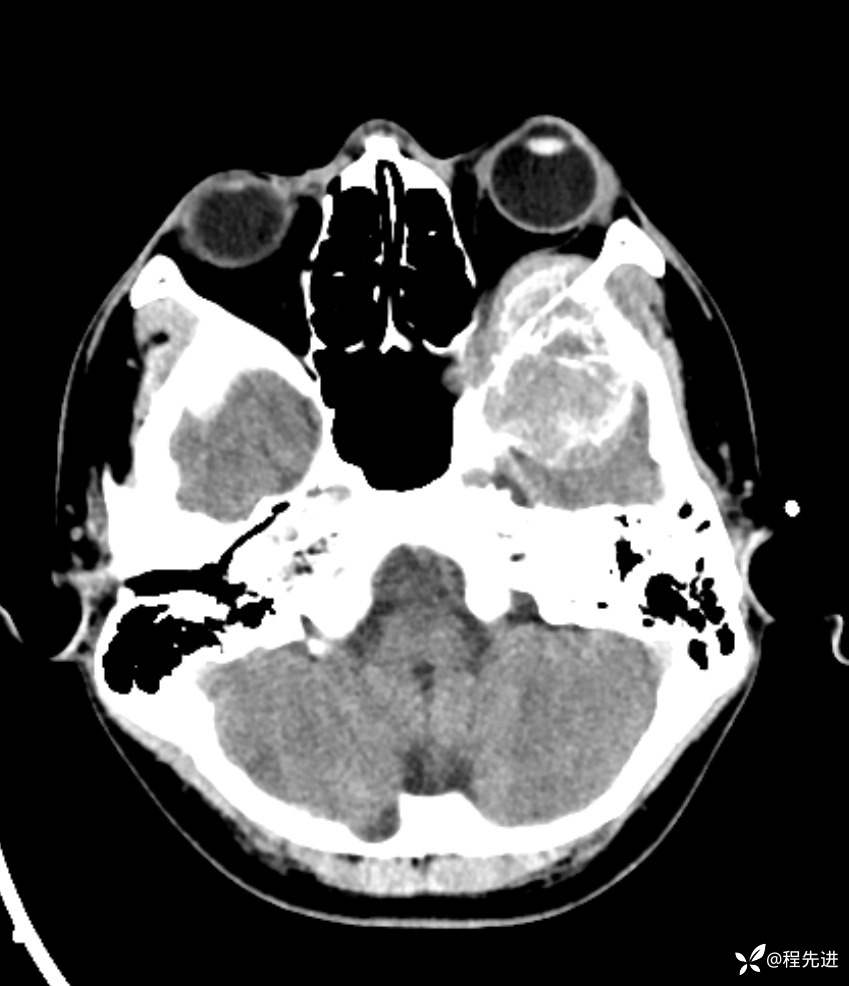

简要病史:左眼视力下降20余天,伴肿胀疼痛不适半月

CT平扫:

脑组织窗: